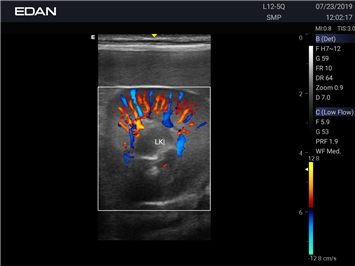

Ветеринарный ультразвук одним нажатием. Система Acclarix AX3 VET разработана с целью обеспечить бескомпромиссную производительность по доступной цене. Наличие уникальных двойных разъемов и двойных аккумуляторов в легком корпусе массой 4,5 кг из магниевого сплава позволяет системе Acclarix AX3 VET удовлетворять все потребности ветеринарных исследований, сохранив низкую стоимость.

EDAN Acclarix AX3 VET - это компактная ультразвуковая система, специально разработанная для ветеринарной практики, сочетающая высокую производительность с доступной ценой.

Передовые технологии визуализации

Качество диагностики:

• Революционная платформа с превосходным разрешением для глубоких структур

• Технология адаптивной визуализации тканей с автоматической оптимизацией

• Специальные настройки для исследования животных разных видов

• Двойные разъемы для быстрой смены датчиков